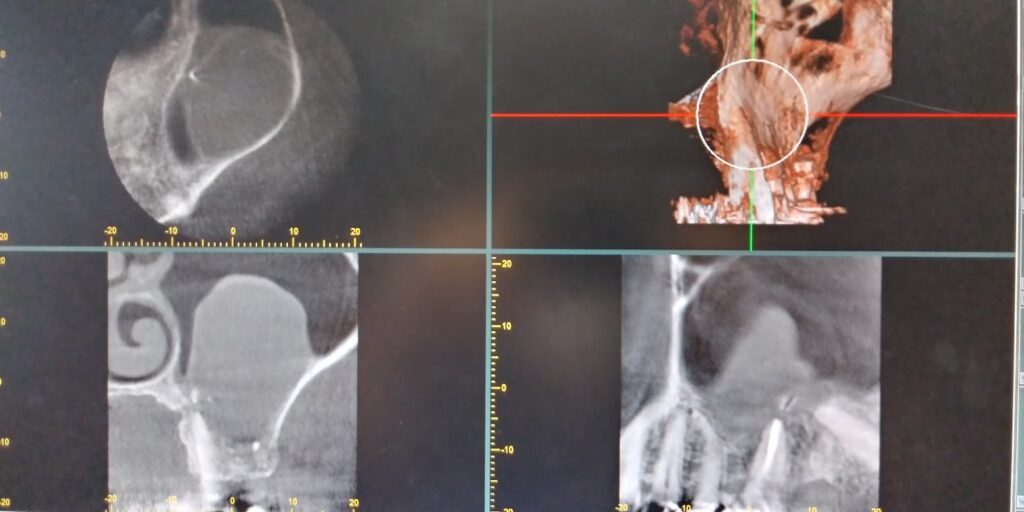

デンタルCTを活用した歯科治療

当院では、デンタルCTを活用し、精度の高い治療を提供いたします。

デンタルCTでは、3次元の立体画像としてあらゆる角度から見ることができます。平面写真だけでは分からなかった症状の原因を追求して、正確な診断、治療につなげるように努力しています。